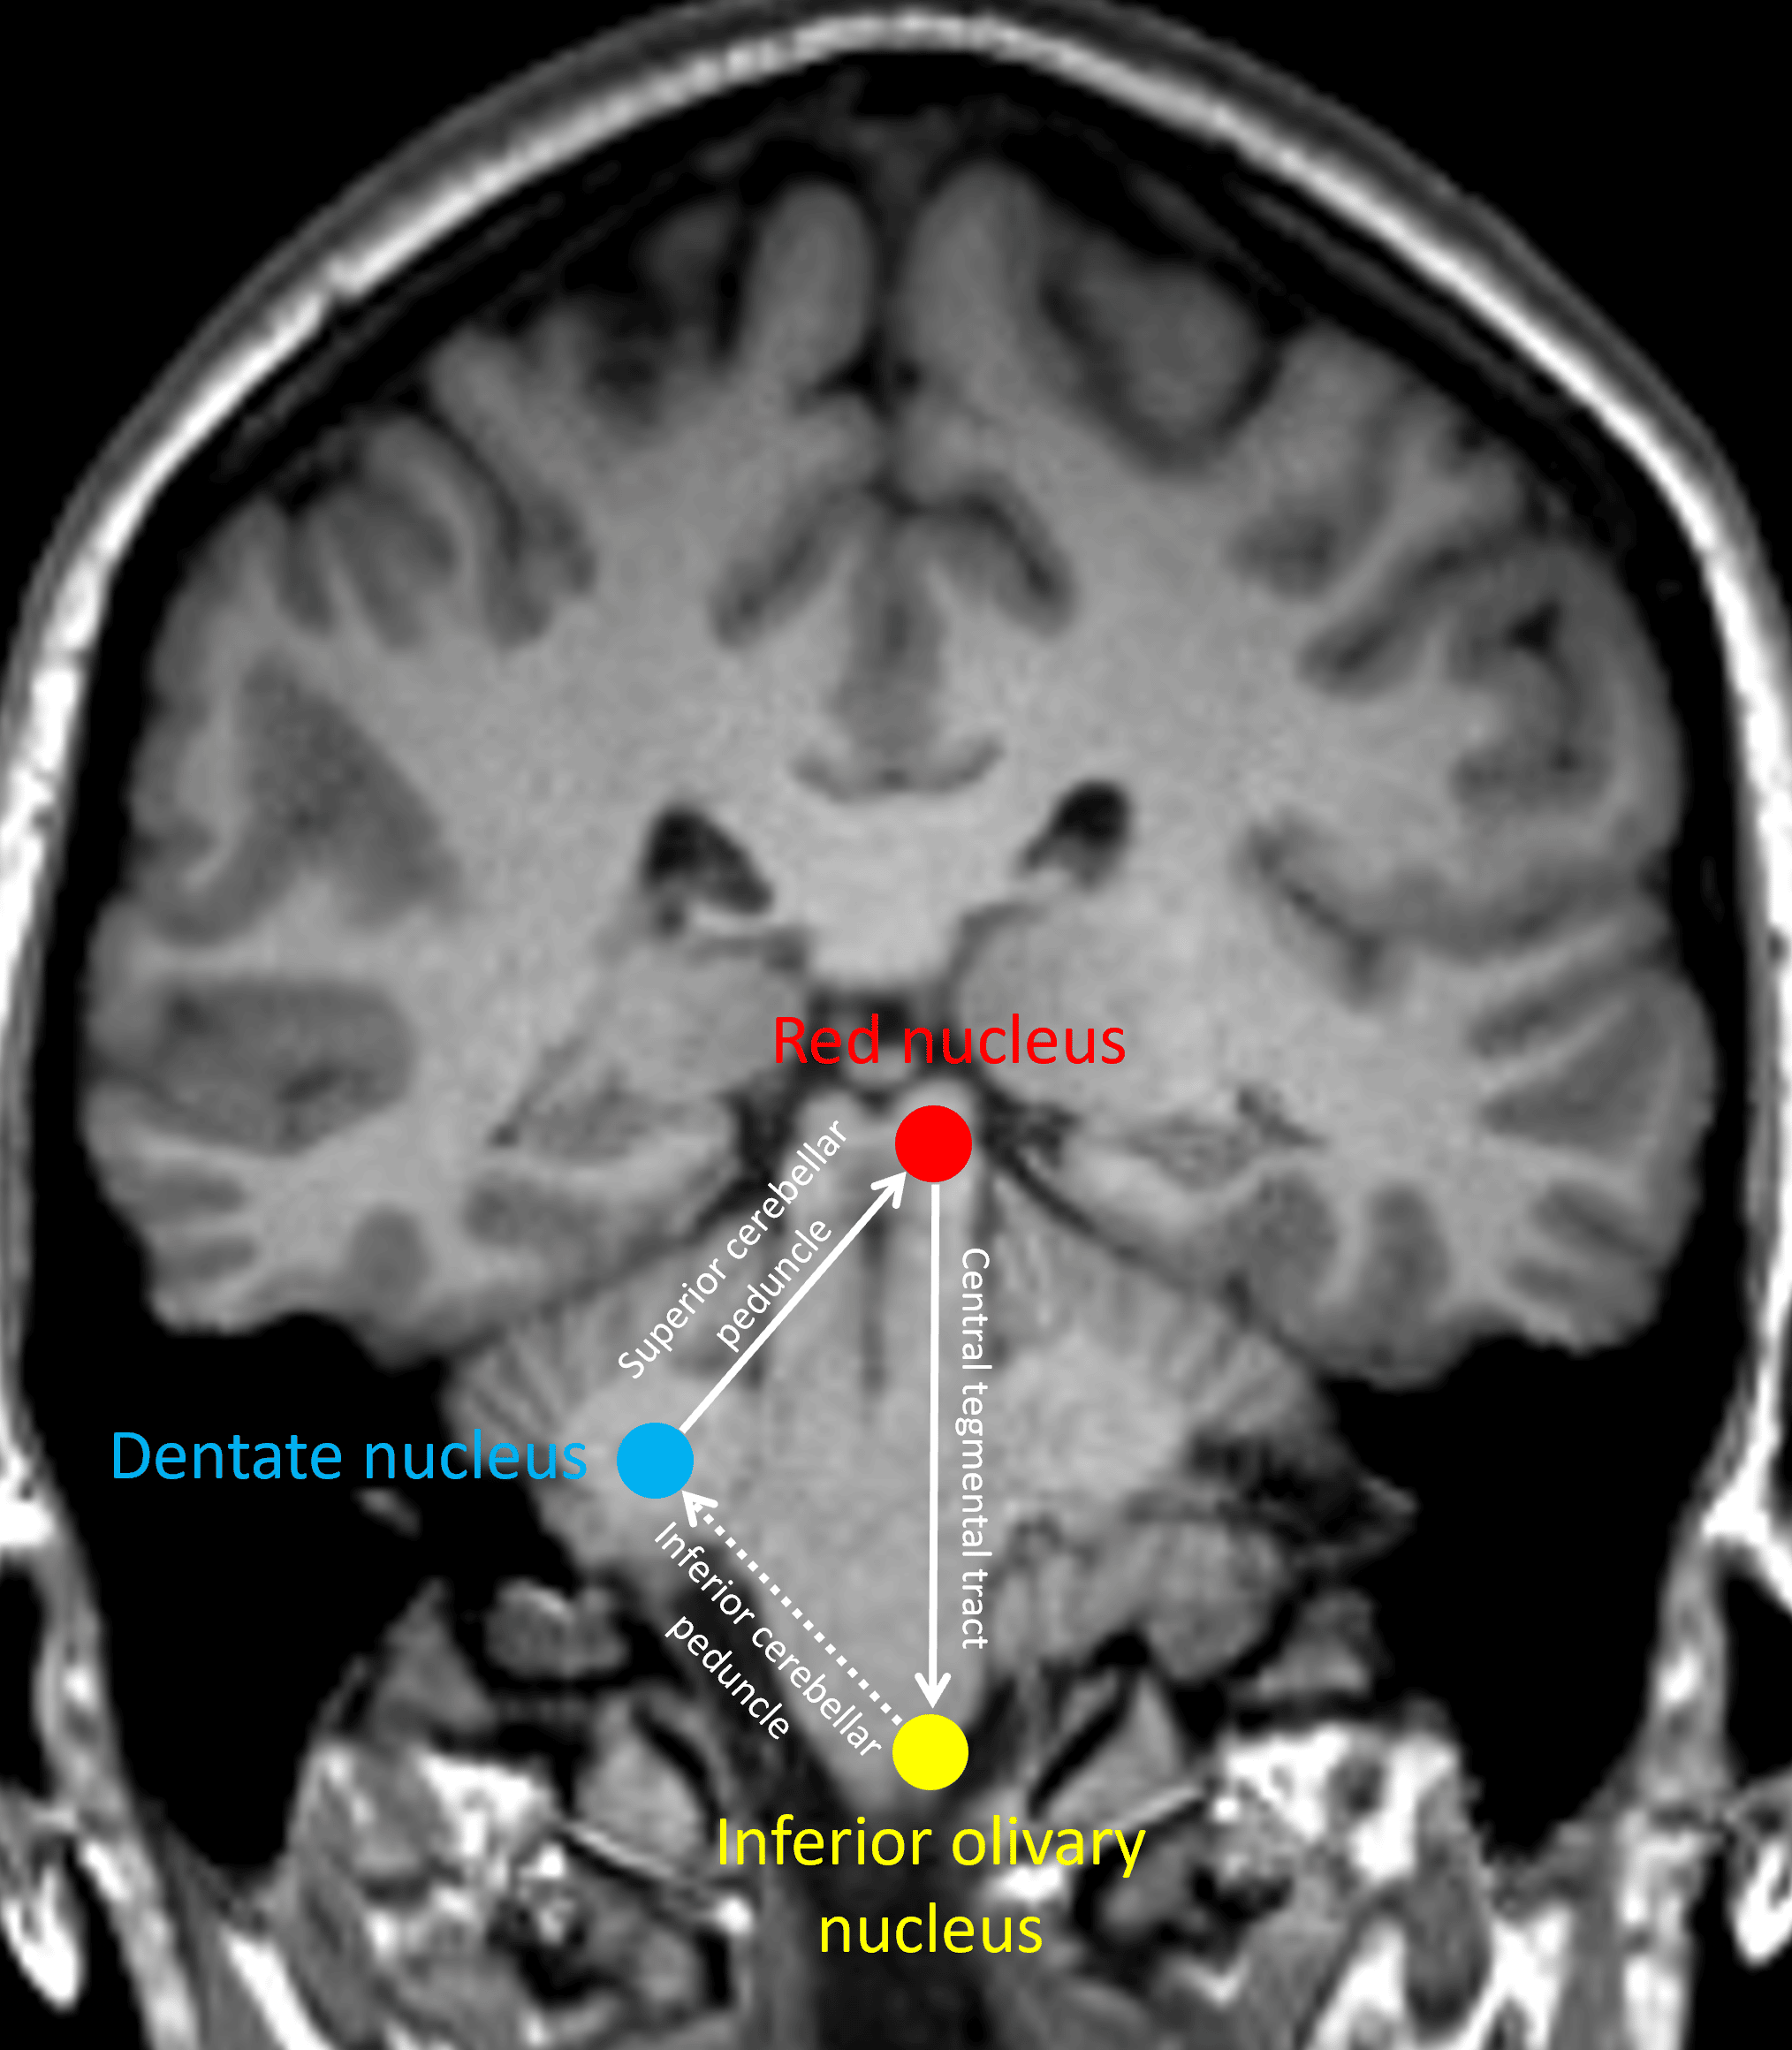

The infamous Guillain-Mollaret triangle.